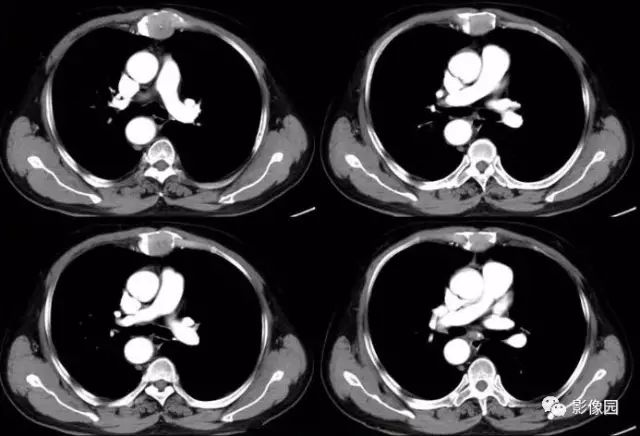

肚肚丫头: 胸骨体局部呈膨胀性骨质吸收破坏,内呈软组织密度影,可见点状钙化,增强扫描呈轻度强化,周围软组织略肿胀。考虑:1.骨巨细胞瘤;2.浆细胞瘤;3.嗜酸性肉芽肿

CT表现:特征性穿凿状、鼠咬状及蜂窝状骨破坏,边缘清楚,骨质疏松,病理性骨折及软组织肿块等表现,骨质硬化及骨膜反应少见。

骨破坏区完全为软组织取代,骨质膨胀,边界清楚,常突破骨皮质形成软组织肿块。增强扫描可见病灶轻中度强化,一般于静脉期达峰值。